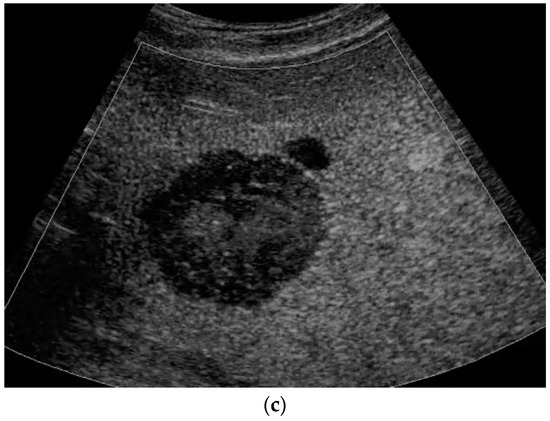

CEUS: HAS is characterized predominantly by nodular peripheral enhancement during the arterial phase and portal venous phase, while diffuse chaotic or reticular enhancement could also be seen. In the late phase, HAS typically shows hypoenhancement, possibly with partial rim-like enhancement or isoenhancement, without centripetal filling [10]. In contrast, typical hemangiomas could be accurately diagnosed by CEUS with peripheral nodular enhancement and centripetal filling, which should be differentiated from HAS (Figure 4).

Figure 4.

A 17-year-old female with a focal liver lesion in the right liver lobe and a small oval cyst in the surrounding area (a). Arterial phase hyperenhancement predominantly in the periphery with a rim and septae-like structures with non-enhancing areas (b) and washout are documented (c). Needle biopsy with histological evaluation revealed angiosarcoma of the liver.